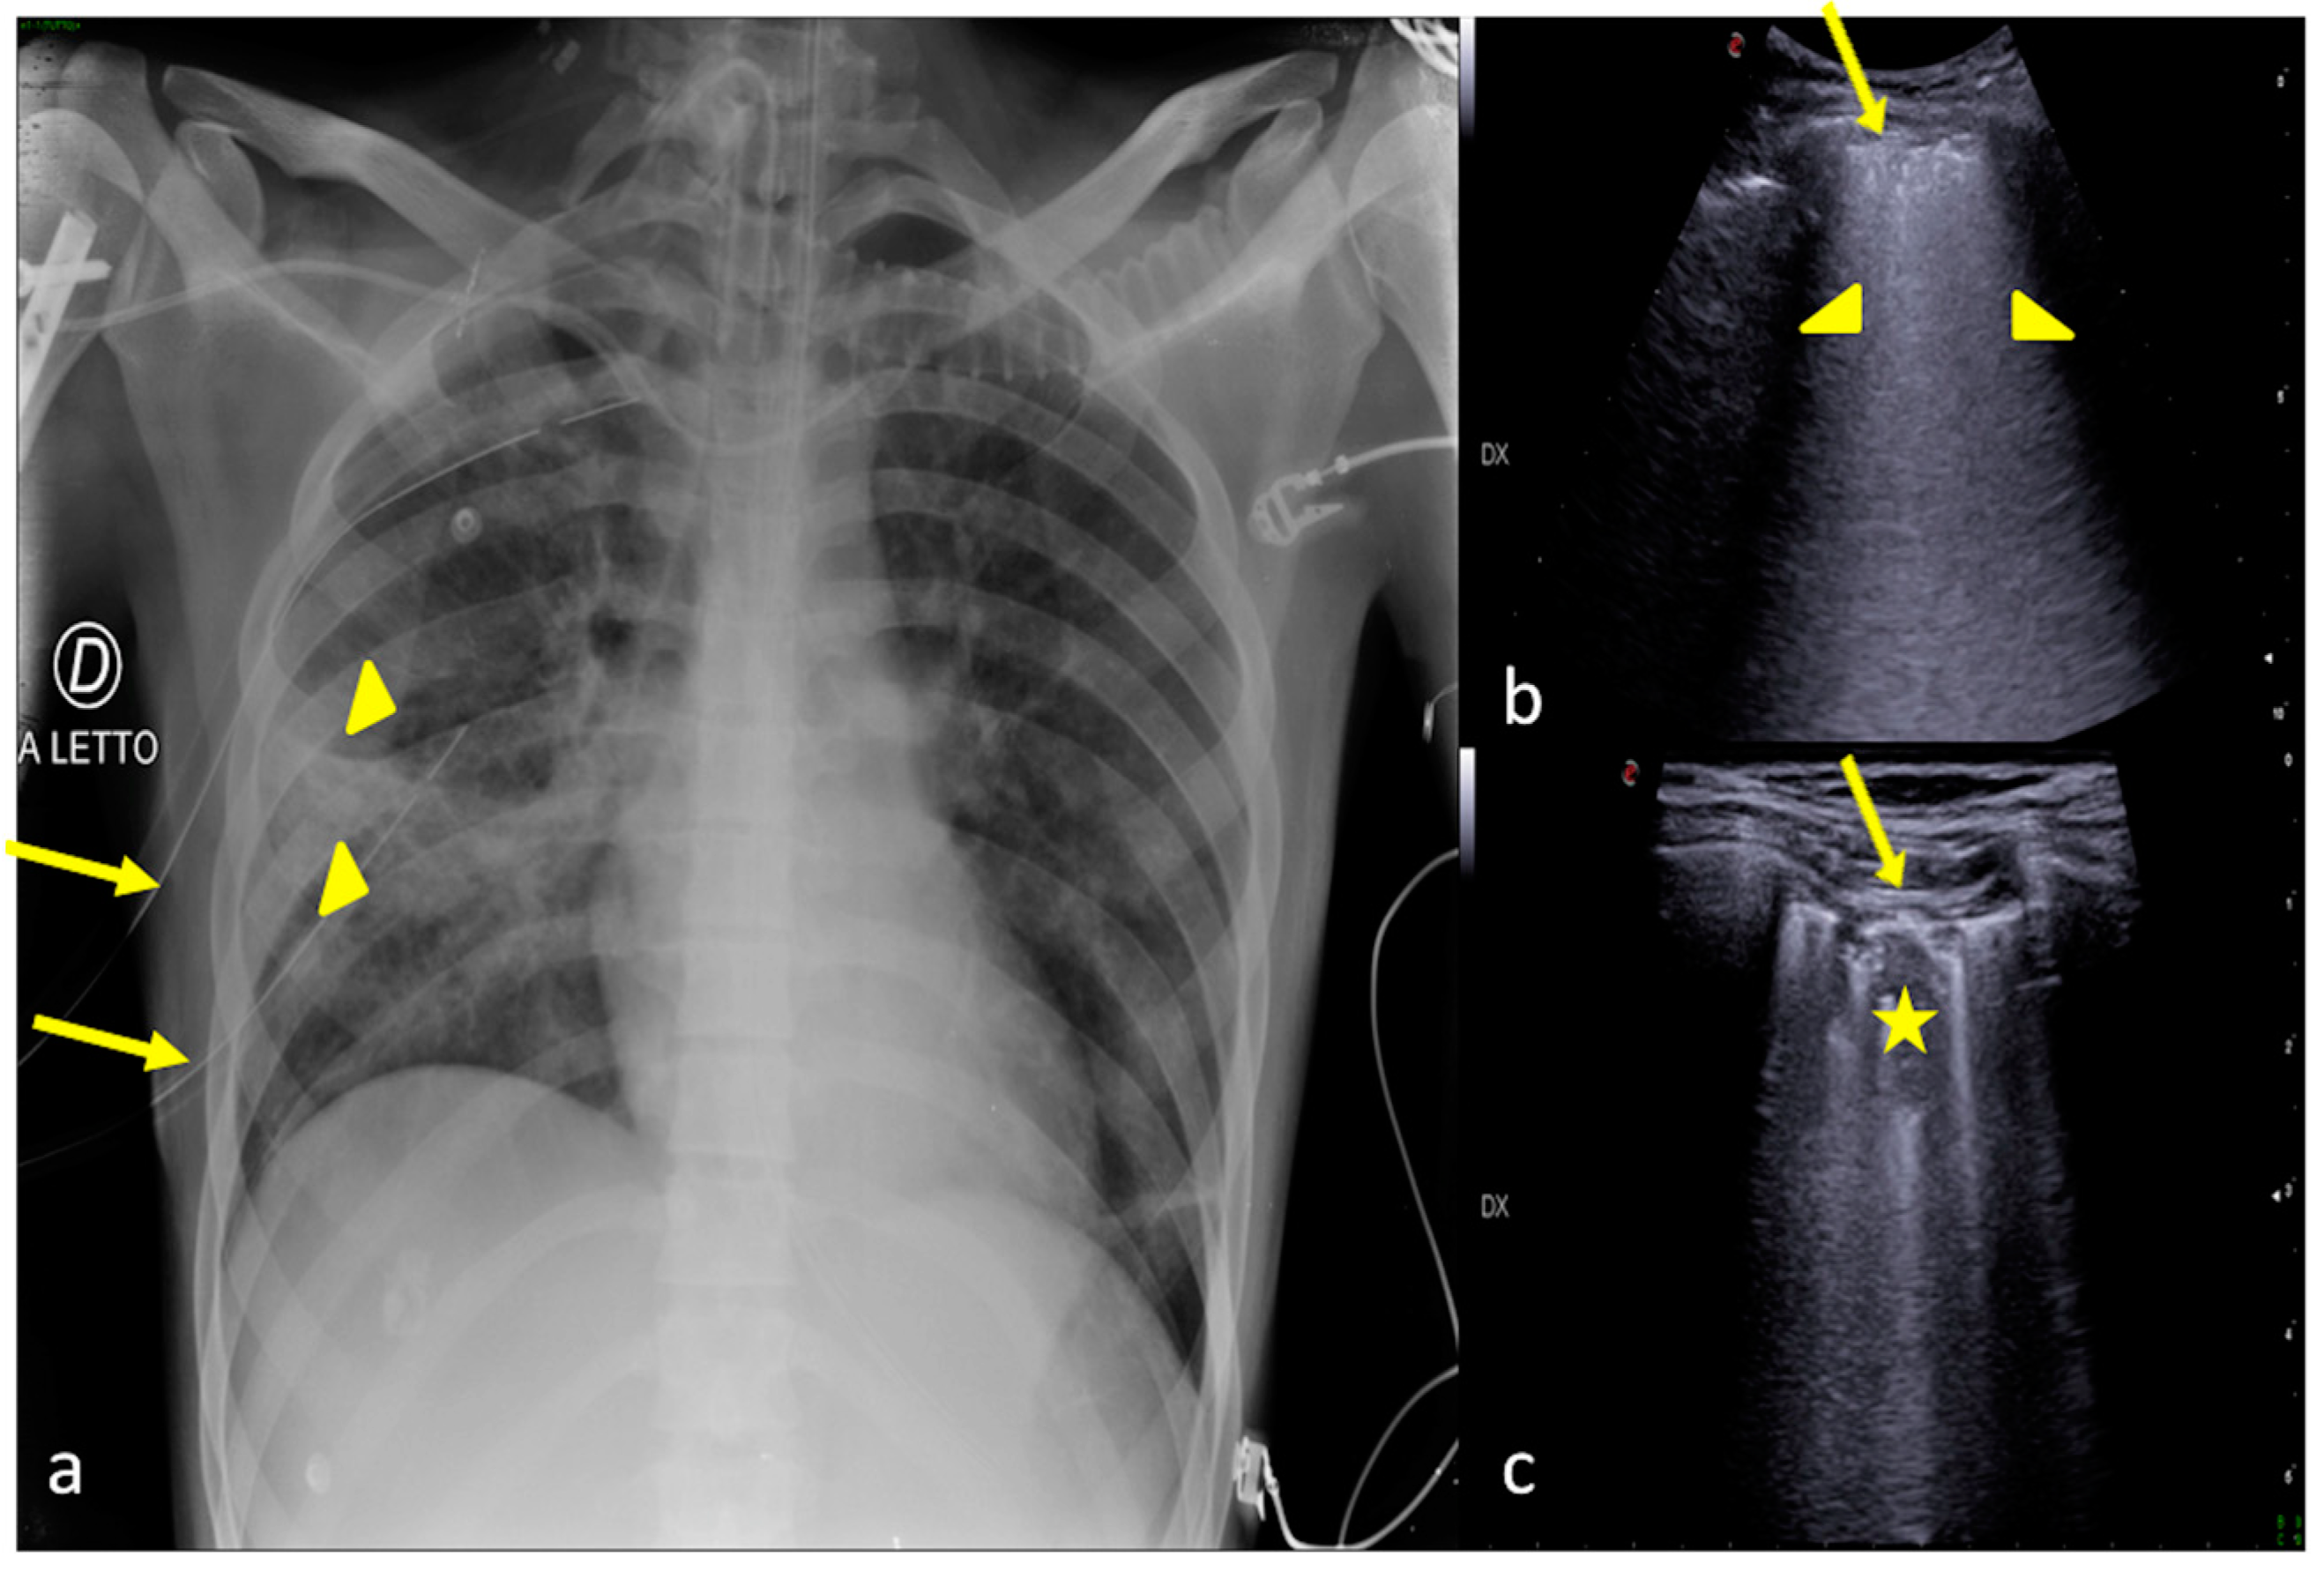

2.1. Atelectasis

2.6. Pulmonary Contusion

3. Confirming or Excluding Pneumothorax and Monitoring its Evolution